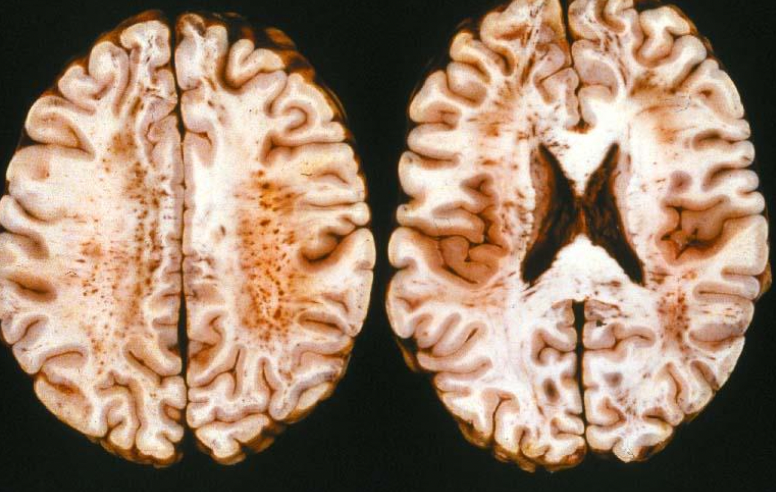

Petechial hemorrhages in white matter